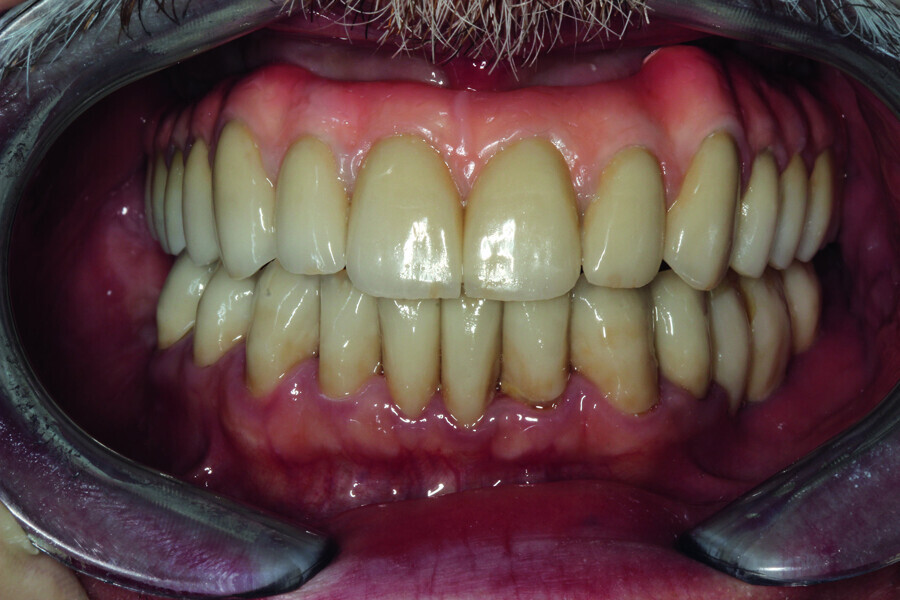

Fig. 27: Final prosthetic restoration in patients’ mouth.

Fig. 28: Patient’s smile at the end of

the treatment.